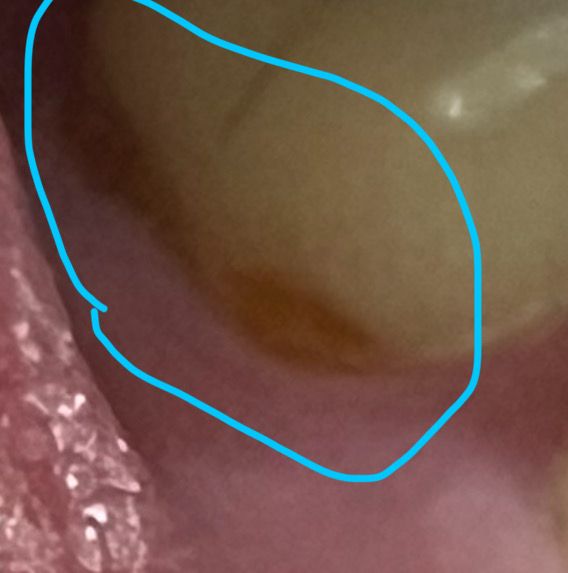

스케일링 후 아랫니 잇몸 경계부에 드러난 갈색 부분이 무엇인가요?

오늘 스케일링을 받았는데 집에 와서 보니 사진처럼 아랫니 뿌리쪽이 갈색인 부분이 보여서 질문드립니다.스케일링이 덜 되어서 치석이 남은걸까요?

아니면 뿌리가 드러난걸까요..?

치석으로 보여지지는 않습니다. 원래 치석이 덮여있어 잇몸이 내려간 부위가 이제 스케일링하고 드러난 것 같습니다. 해당 부위 약간 마모가 있는 것으로 보입니다.

사진상으로는 애매하지만 치석이 아니라 상아질로 보입니다. 치아의 머리 부위는 가장 겉층의 투명+하얀 에나멜 층과 그 뒤에 노랗고 갈색빛의 상아질 층이 있는데요. 치경부(치아의 목 부위로 잇몸 부근)의 에나멜 결손 시( 치경부 마모나 굴곡파절로 인해) 저렇게 상아질이 드러나보입니다.

결손의 양상으로 보아 abfraction 굴곡파절로 보이는데요. 상아질은 에나멜에 비해 마모저항성이 낮기 때문에 레진이나 gi등으로 수복해 추가적인 결손을 방지해주는 것이 좋습니다.

해당부위는 치아의 옆면에 마모증이 생긴것으로 보입니다.

마모증은 양치질을 할때 너무 세게 할때 생길수 있기때문에 양치질을 약하게 하는것이 좋습니다.

또한 마모증이 있는 부위는 치과용 재료로 충전을 해줄수 있습니다.